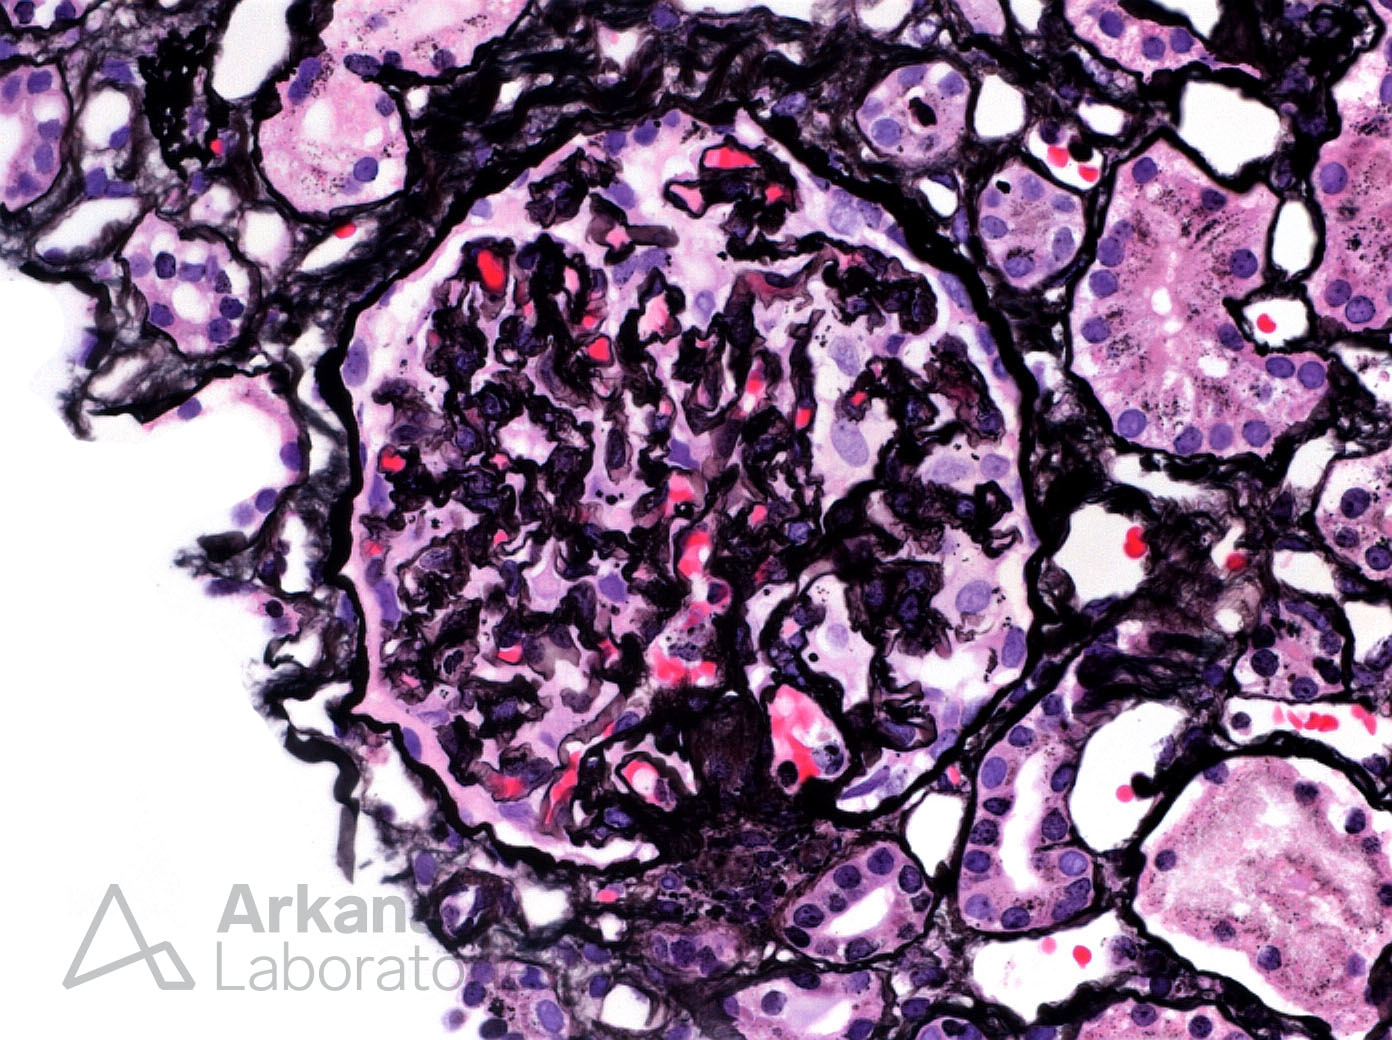

Previous Image Next Image Glomerular Basement Membrane Corrugation (An Ischemic Change) in Scleroderma Renal Crisis Like Loading...